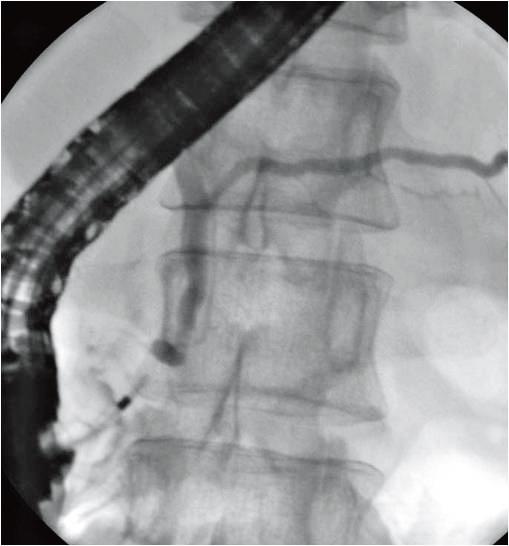

あとは、CTで肝臓には何もなくて胆嚢がよくわからない(?)、ERCPで胆管・膵管とも拡張なく綺麗に描出されている(一方で胆嚢は描出されてない)、、といったあたりが読めれば、b 胆嚢癌とわかる。